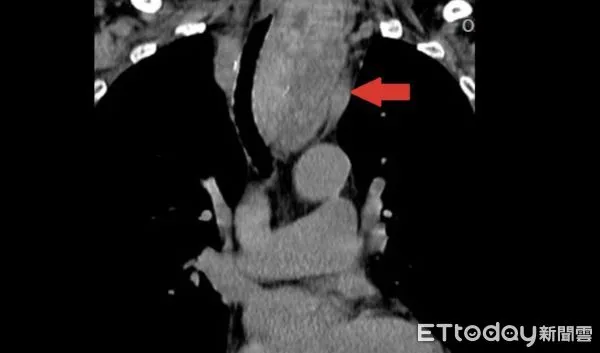

▲黃女士甲狀腺結節如芭樂大,已經擠壓氣管。(圖/醫師提供)

74歲黃女士10年前因右側甲狀腺結節問題,在醫院接受手術切除,3年前又發現左側結節逐漸增大,出現吞嚥困難、頸部腫脹,再度檢查發現結節已經侵犯胸腔,氣管已經被13公分如「芭樂般大」的結節壓迫偏移至右側,進一步安排手術切除。

收治該病例的台北慈濟醫院胸腔外科醫師洪嘉聰指出,黃女士左側結節切片數次均屬良性,原本想說在未影響生活的情況下,選擇持續觀察,但之後因出現不適症狀,檢查發現已經擠壓氣管,雖呼吸未受影響,但仍評估手術切除。